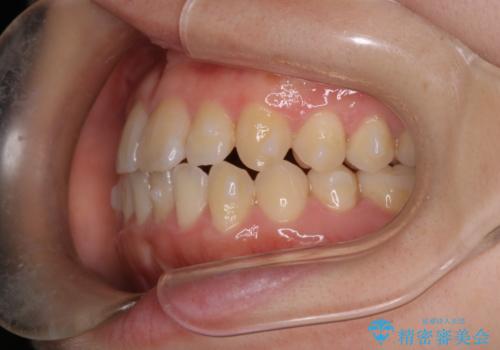

【インビザライン】前歯のがたつきを目立たない装置で治療

- 前歯の叢生を主訴に来院されました。目立たない装置を希望されたためインビザラインで治療を行いました。

IPRと拡大をし、叢生を治しました。右上2番は反対咬合でしたが短期間できれいに治りました。